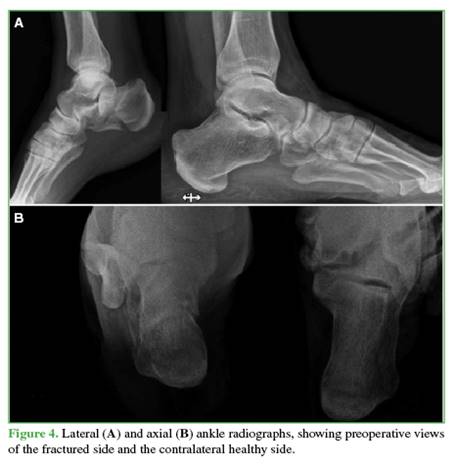

The number and orientation of the 6.5/7 mm screws will depend on the fracture lines. The objective of these screws is to support the greater tuberosity with the calcaneal body and the lesser tuberosity, also creating a “scaf-folding” that provides stability to the posterolateral articular facet (Figures 4-6).

The mean Böhler angle showed significant differences between the contralateral healthy calcaneus (30.76° ± 5.71°) and the preoperative measurement (14.05° ± 6.60°). However, the differences between the healthy side (30.76° ± 5.71°) and the postoperative values, both immediate (29.50° ± 5.96°) and remote (29.86° ± 6.51°), were minimal. The 25th, 50th, and 75th percentiles were also considered. Student’s t-tests for independent samples confirmed that there was no statistically significant difference between measurements on the healthy contralateral calcaneus and the immediate postoperative values (95% confidence interval [CI], p = 0.571, d = 0.216) or the remote values (95% CI, p = 0.700, d = 0.147), whereas there were significant differences compared to the preoperative values (95% CI, p < 0.001, d = 2.708).

The mean Gissane angle showed differences between the contralateral healthy calcaneus (119.03° ± 6.99°) and the preoperative value (110.31° ± 10.01°). However, the differences between the healthy side (119.03° ± 6.99°) and the immediate (118.85° ± 7.54°) and remote (119.00° ± 7.43°) postoperative values were not statistically significant. Student’s t-tests for independent samples confirmed that there was no statistically significant difference between the healthy contralateral calcaneus and the immediate (95% CI, p = 0.948, d = 0.0248) or remote (95% CI, p = 0.992, d = 0.004) postoperative values, while there was a significant difference compared to the preoperative values (95% CI, p = 0.013, d = 1.010).

The mean calcaneal length showed minimal differences between the contralateral healthy calcaneus (77.61 ± 8.25), the preoperative value (76.01 ± 8.47), and the immediate (78.26 ± 8.01) and remote (76.99 ± 7.56) postoperative values. Student’s t-tests for independent samples confirmed that there were no statistically significant differences between the healthy contralateral calcaneus and the preoperative value (95% CI, p = 0.617, d = 0.191), the immediate (95% CI, p = 0.835, d = –0.080), or the remote (95% CI, p = 0.836, d = 0.078) postoperative values.

The mean calcaneal width showed differences between the contralateral healthy calcaneus (36.94 ± 4.09) and the preoperative value (44.13 ± 9.36). However, the differences between the healthy side (36.94 ± 4.09°) and the immediate (39.17 ± 4.77) and remote (38.99 ± 5.16) postoperative values were minimal.

Although the ELA offers better fracture exposure and should theoretically yield superior reductions, STA with cannulated screws has been shown to be more reliable in restoring Gissane and Böhler angles. Pitts et al.23 compared 51 DIACFs treated with STA and cannulated screws to 23 treated with ELA and found no significant differences. Wang et al.21 argue that cannulated screws ensure better reductions In our series, postoperative Gissane and Böhler angles were not significantly different from the contralateral healthy calcaneus, suggesting that limited exposure does not compromise reduction quality. Sanders et al. recommend CT imaging to evaluate postoperative PLAF reduction and classify outcomes based on the residual step height: reductions are considered anatomic when the step is ≤1 mm and near-anatomic when it measures between 1 and 3 mm.6 In our series, STA enabled us to achieve 9 anatomic and 5 near-anatomic reductions; no steps >2 mm were recorded. We believe that the visualization of the PLAF provided by the STA is sufficient for adequate reduction.